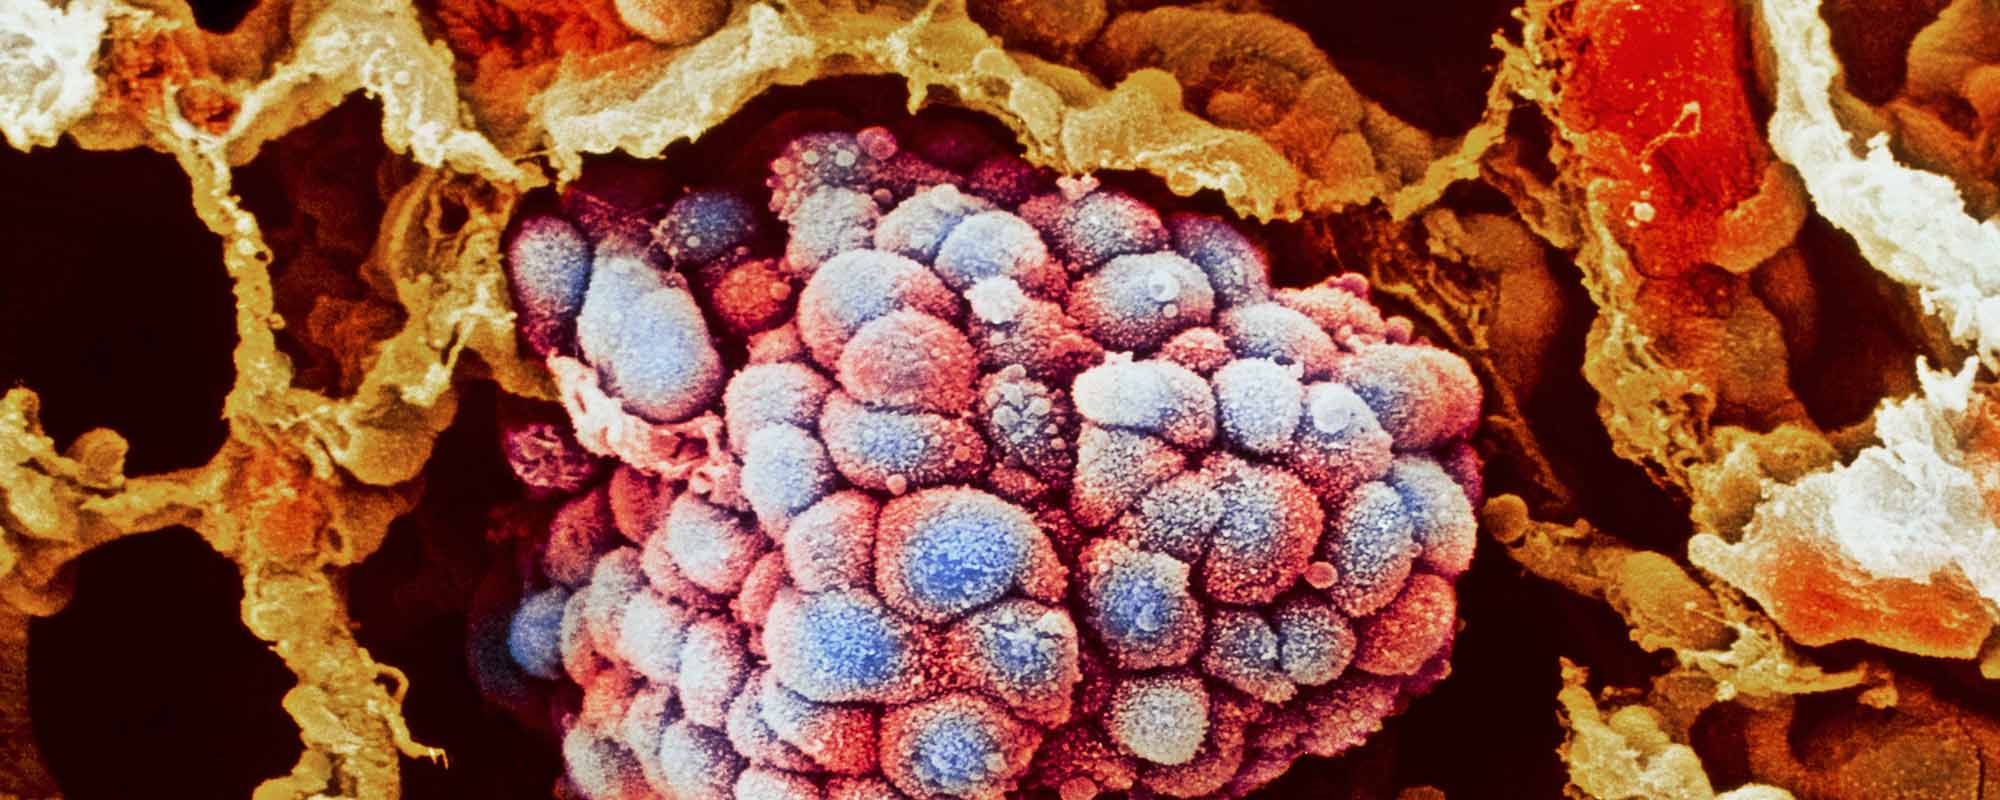

Раковая шишка – это заболевание, которое поражает кожу и слизистые оболочки. Она может возникнуть в различных частях тела и иметь различные внешние проявления. В данной статье мы представляем вам многочисленные фотографии раковых шишек, чтобы вы могли узнать, как они выглядят.

Фото раковой шишки на теле

Раковые шишки могут возникать не только на лице, но и на других частях тела. На фотографиях вы можете увидеть примеры раковых шишек на шее, руках, ногах и туловище. Обратите внимание на различные формы и размеры раковых шишек, а также на их внешний вид.